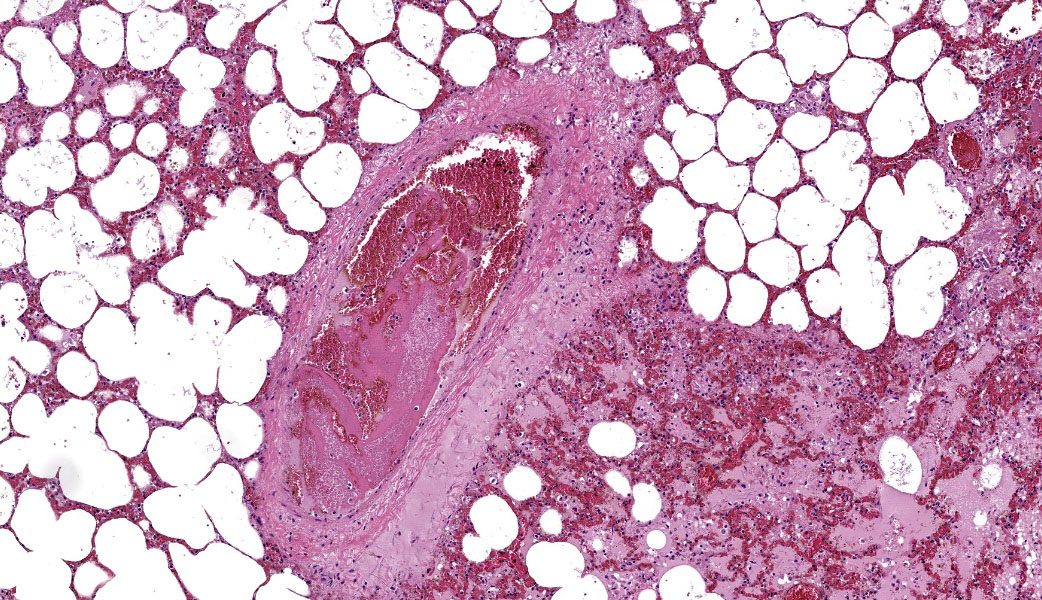

Lung: Pneumonia, bronchointerstitial, necrotizing and fibrinosuppurative, acute, multifocal to coalescing, marked, with thrombosis, edema, and hyaline membranes.

Typical pathological changes in equids with viral pneumonia include pulmonary consolidation in a lobular pattern separated by unaffected or overinflated lung lobules, or less commonly, a diffuse pattern of pneumonia.1 EIV infections complicated by secondary bacterial infections are characterized by fibrinosuppurative exudate and pulmonary consolidation, mostly restricted to the cranioventral pulmonary lobes (bronchopneumonia).1,12,13 Histopathologically, acute stages typically reveal rhinitis and tracheitis with epithelial necrosis and infiltrates of lymphocytes in the lamina propria. Subacute to chronic lesions consist of epithelial hyperplasia and squamous metaplasia.6,11 Affected lungs exhibit bronchointerstitial pneumonia with hyaline membranes in the alveoli, type II pneumocyte hyperplasia, and necrotizing bronchitis/bronchiolitis. Secondary bacterial bronchopneumonia may also develop.4,6,12

Determining differentials in a case of viral pneumonia in any species requires a working knowledge of viral pathogenesis and target cells to refine the list of potential offenders. In this case, the most striking hallmarks for influenza virus include the end-airway epithelial necrosis and patchy areas of hemorrhage. Influenza is both endotheliotropic and epitheliotropic and, while it affects epithelial cells in the upper airways, it has unique tropism for the type I and type II pneumocytes of the alveoli as well. It causes significant destruction to end-airways as a result. This key difference can help separate an influenza infection from other pneumotropic viruses, such as calicivirus in cats. (Feline calicivirus infection of the lung can look nearly identical to an H5N1 influenza virus infection in a cat, but the state of the end airways can help clue in the pathologist to which virus is most likely and can assist in decision-making for next testing steps. The more virulent strains of feline calicivirus can cause severe interstitial pneumonia, but they do not cause necrosis of end airways the way that influenza does.)

Grossly, an influenza-infected lung has a ?checkerboard? appearance with random, alternating areas of dark red atelectasis and light pink, aerated lung. This pattern manifests because influenza does not uniformly infect every cell it comes into contact with due to varied densities of sialic acid receptors on the host cells. Dark red to purple areas of consolidation represent collapsed alveoli whose airway has been clogged by exudate and which can no longer pass air through to the alveoli.. These solidified, dark red sections contrast sharply with the lighter-colored, air-filled alveoli.